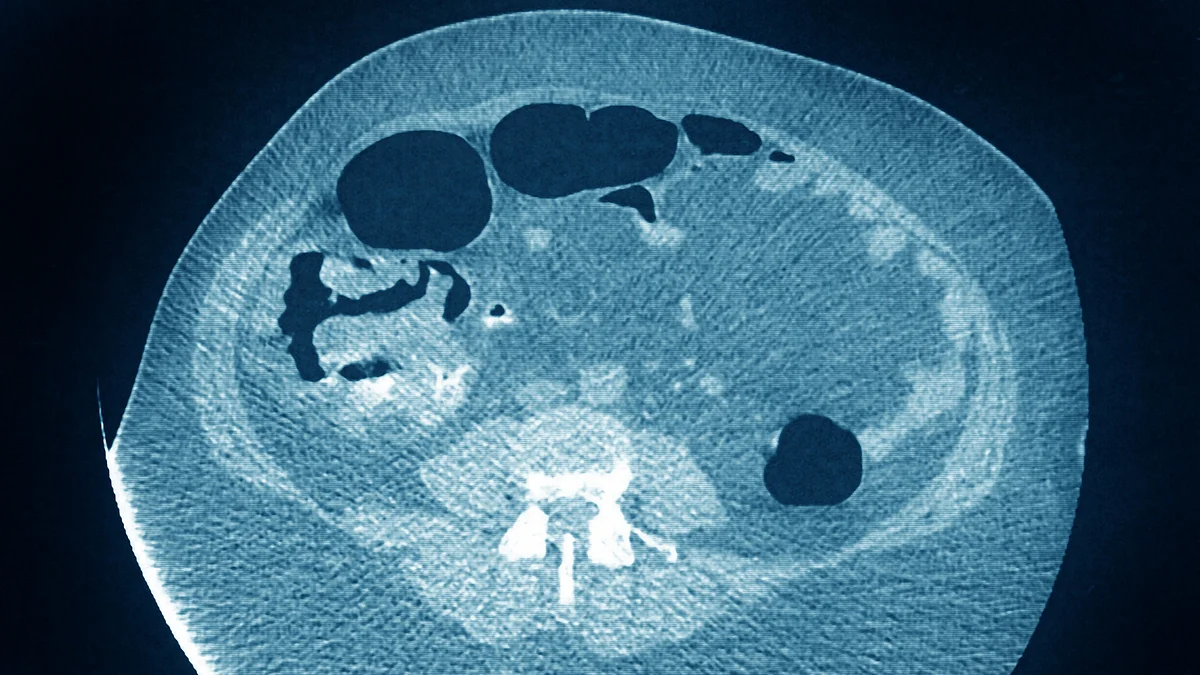

Researchers have found new genes that put people at higher risk for colon and rectal cancer, an advance that may aid efforts towards prevention and treatment of this prevalent malignancy.

The study, published in the Journal of the National Cancer Institute, found that oncogenic roles for two previously unreported genes, TRPSI and METRNL, and confirmed cancer susceptibility with another recently reported gene, C14orfl66.